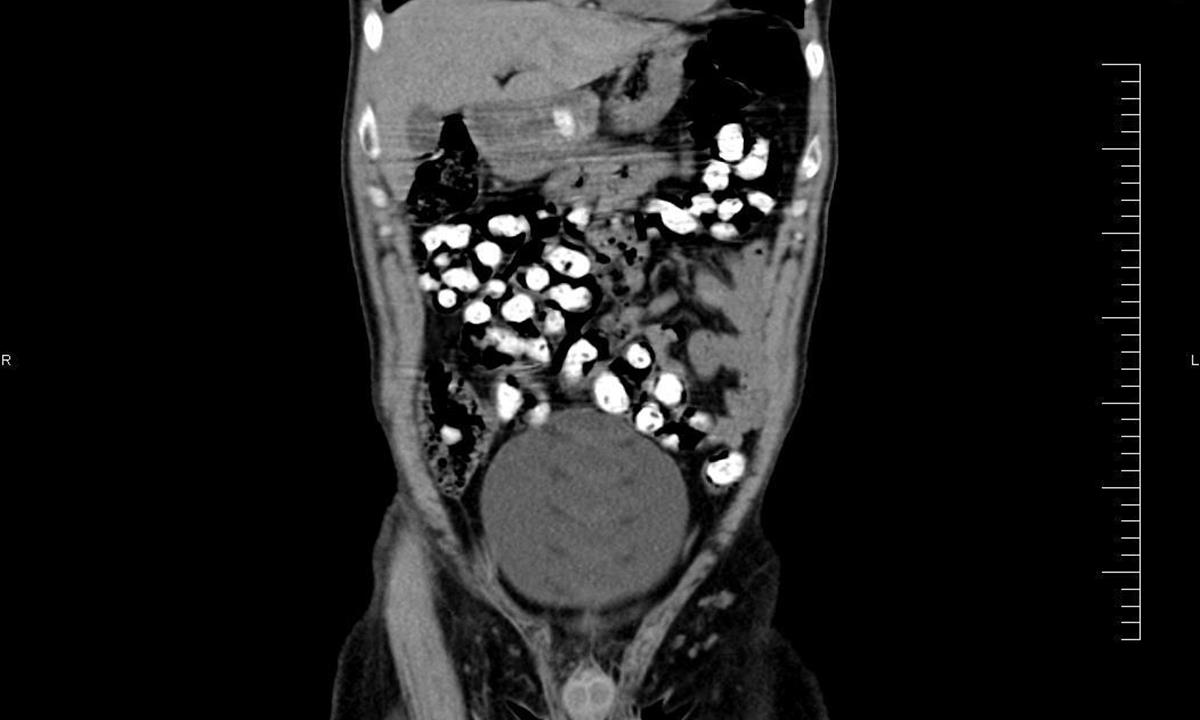

Ke kontrole byl polykač celníky vytipován na základě provedené rizikové analýzy daného letu. Prvotní podezření na pašování drog celníkům potvrdily kontrolní stěry z rukou pašeráka.  Při důkladné kontrole jeho zavazadel a osobní prohlídce nebyly drogy nalezeny, proto bylo provedeno následné rentgenové vyšetření (viz.foto).

Postupně z těla pašeráka vyšlo všech 107 kontejnerků naplněných tuhou hmotou černé barvy. Chemická látka při provedení detekční zkoušky pozitivně reagovala jako opiát. Celková hmotnost všech kapslí včetně drogy je 856 gramů. Určení vlastní hmotnosti a druhu zajištěné drogy je předmětem další odborné expertízy. Podle zkušeností celníků se s největší pravděpodobností jedná o surové opium. Tento druh drogy není na českém trhu obvyklý a zřejmě byla určena k distribuci v jiné zemi.